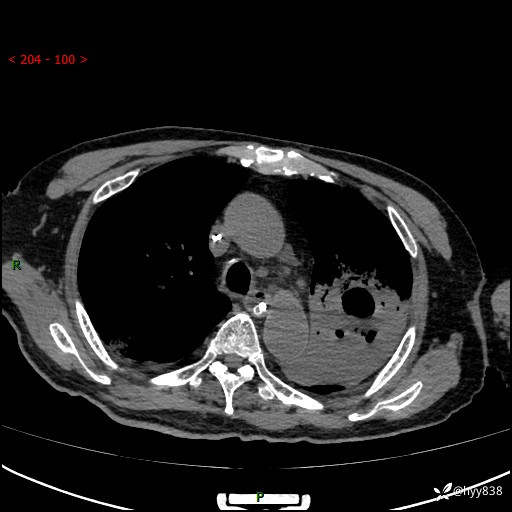

胸部CT复查(2024.8.5)